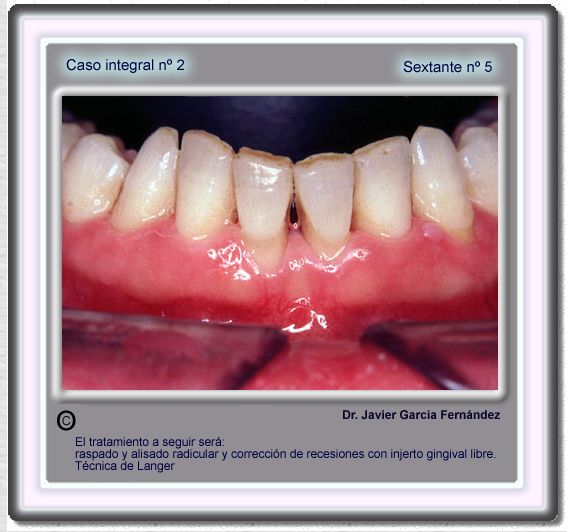

image 71